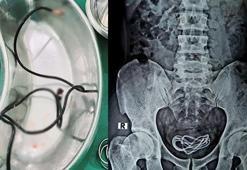

Tıp dünyası şaşkın! Mesanesinden bir metre uzunluğunda şarj kablosu çıktı

Tıp dünyası şaşkın! Mesanesinden bir metre uzunluğunda şarj kablosu çıktıHindistan’da karın ağrısı şikayetiyle hastaneye giden ismi açıklanmayan bir kişinin mesanesinde şarj kablosu tespit edildi. Özel operasyonla kişinin vücudundan çıkarılan şarj kablosu tıp dünyasını da şaşırttı.